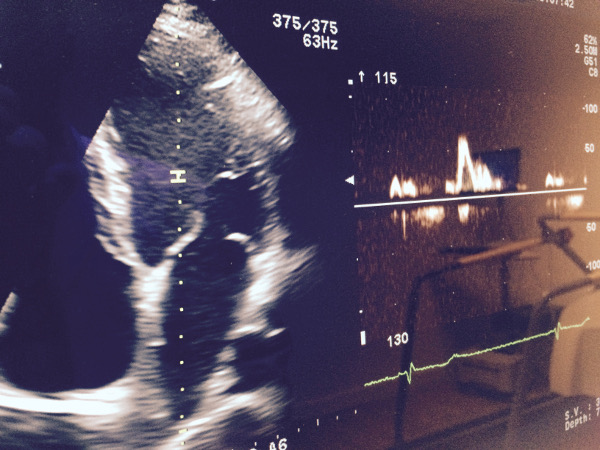

DIAGNÓSTICO POR ULTRASONIDOS. ECOGRAFÍA

Los estudios del cuerpo realizados con ultrasonidos por personal experto y un equipamiento avanzado, permiten la producción de imágenes de calidad de cualquier parte del cuerpo humano. Un examen de ultrasonidos utiliza una instrumentación denominada transductores, los cuales introducen en los tejidos del cuerpo ondas de sonido de alta frecuencia que detectan los ecos producidos cuando estas saltan sus estructuras internas. Los diferentes tejidos del cuerpo reflejan los ecos de forma diferente y un software específico genera imágenes que se visualizan en el monitor y son analizadas por el radiólogo. Leer más...

Pruebas diagnósticas efectuadas con ultrasonidos:

• Estudios de abdomen

• Estudios de vesícula

• Tiroides

• Mama

• Estudios del útero

• Vasos sanguíneos

• Estudios musculoesqueléticos

UNIDAD DE CARDIOLOGÍA AVANZADA

ecocardiografia aviles

La unidad de cardiología avanzada le proporciona uno de los servicios médicos más eficientes y completos de Asturias. Nuestros esfuerzos están encaminados a proporcionar una atención de la máxima calidad, a la vanguardia de los últimos avances y comprometido con las necesidades de atención de los pacientes y sus familias. La unidad atenderá integralmente sus necesidades para la prevención, el diagnóstico y la rehabilitación de la enfermedad cardiovascular gracias a un excelente equipo médico y una tecnología de última generación y de prestigio.